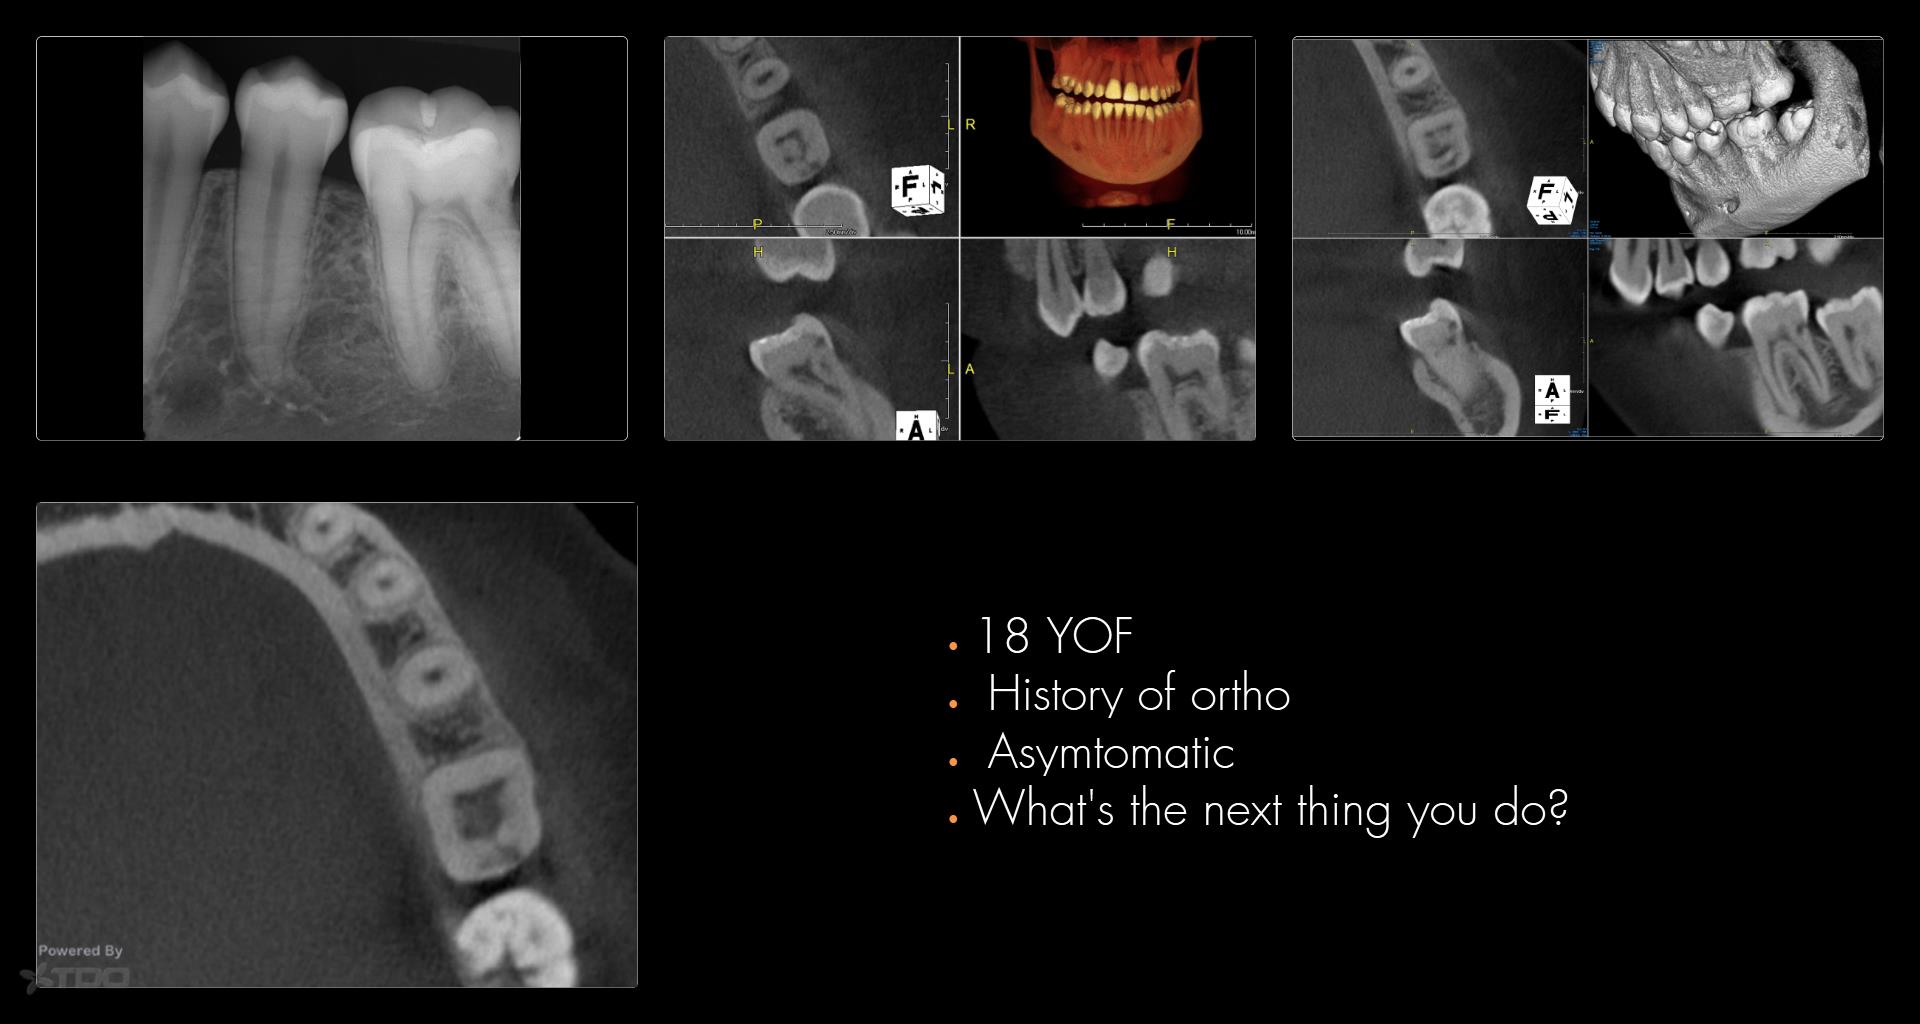

The answer I wanted, given the history of ortho, is that you want to scan other areas of the mouth to see if other areas are involved as well.

For example in this same case…….

Given what we know, and being mindful of all we don’t know, my decision of no treatment is dominated by the consideration of a Class III ECIR with very evident furcal evidence of resorption (where there is no access to the vascular channels) and hence the “smartest bet” is avoid the impulse to be a hero.